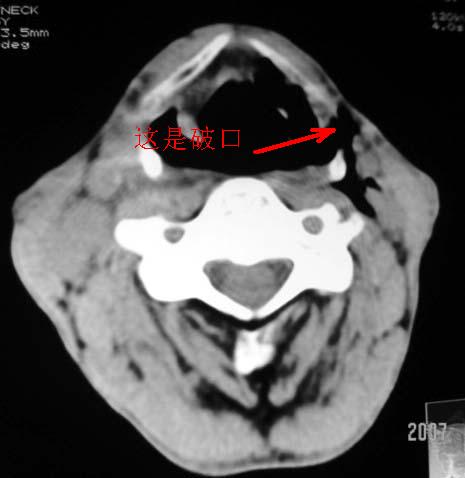

以下是引用dyqct在2007-4-20 16:19:00的发言:[br]考虑:1、左侧梨状窝区破裂伴左颈深、浅部气肿。[br] 2、右侧甲状腺区血肿(请追问病史是否伤及右颈部)。[br] 3、建议病情稳定后增强扫描除外右侧甲状腺腺瘤。